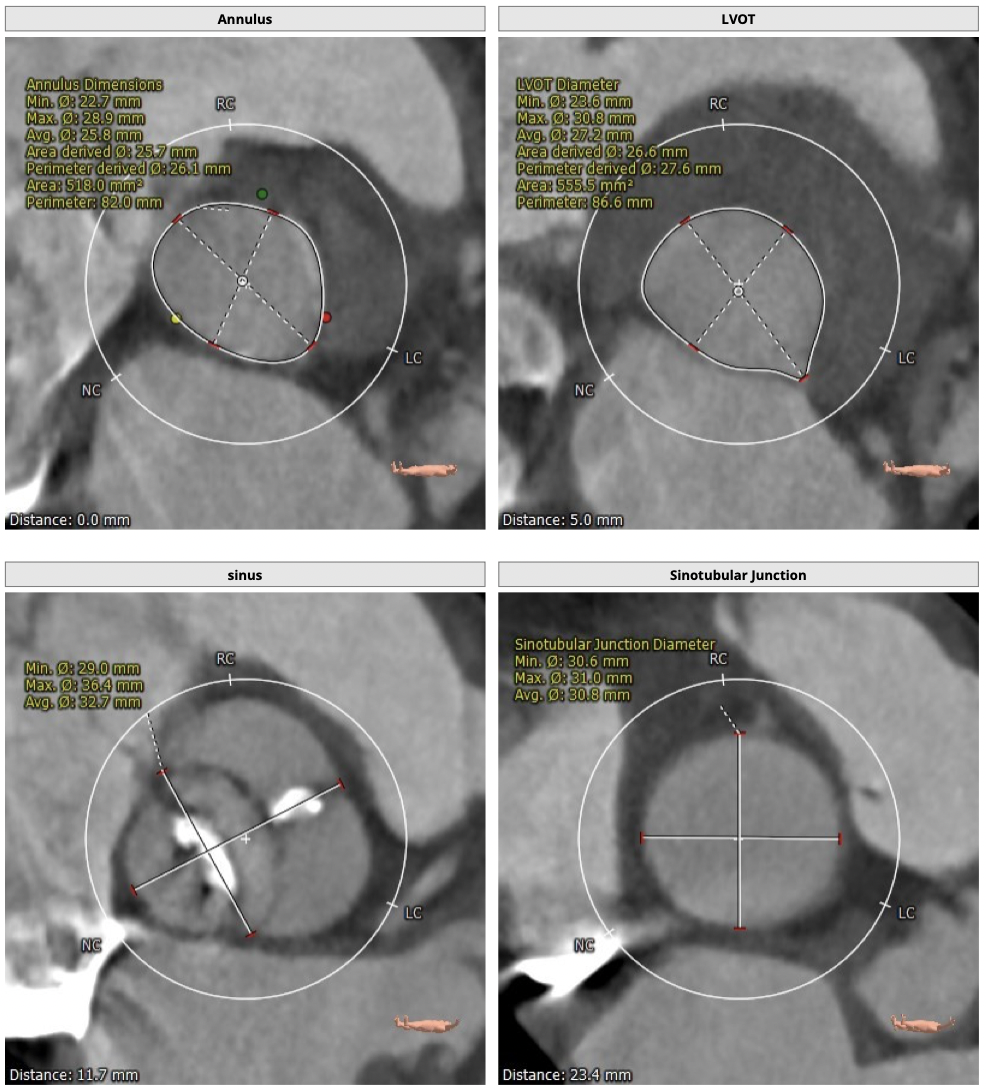

主动脉CT

图片

手术策略

CT分析:

*患者为TYPE1型二叶瓣,左右钙化融合,冠脉高度高,法式窦结构可,心脏角度约50°,左室大小可,心肌增厚,升主动脉未见明显增宽。主动脉弓部走形较平缓,右侧股动脉可作为主入路。

制定策略:

经分析研判,拟从右侧股动脉穿刺入路,使用23mm球囊预扩,选用L29号的VenusA-Valve瓣膜,采用VenusA-Plus可回收输送系统进一步确保手术安全,瓣膜释放后结合造影和超声情况,决定是否后扩。